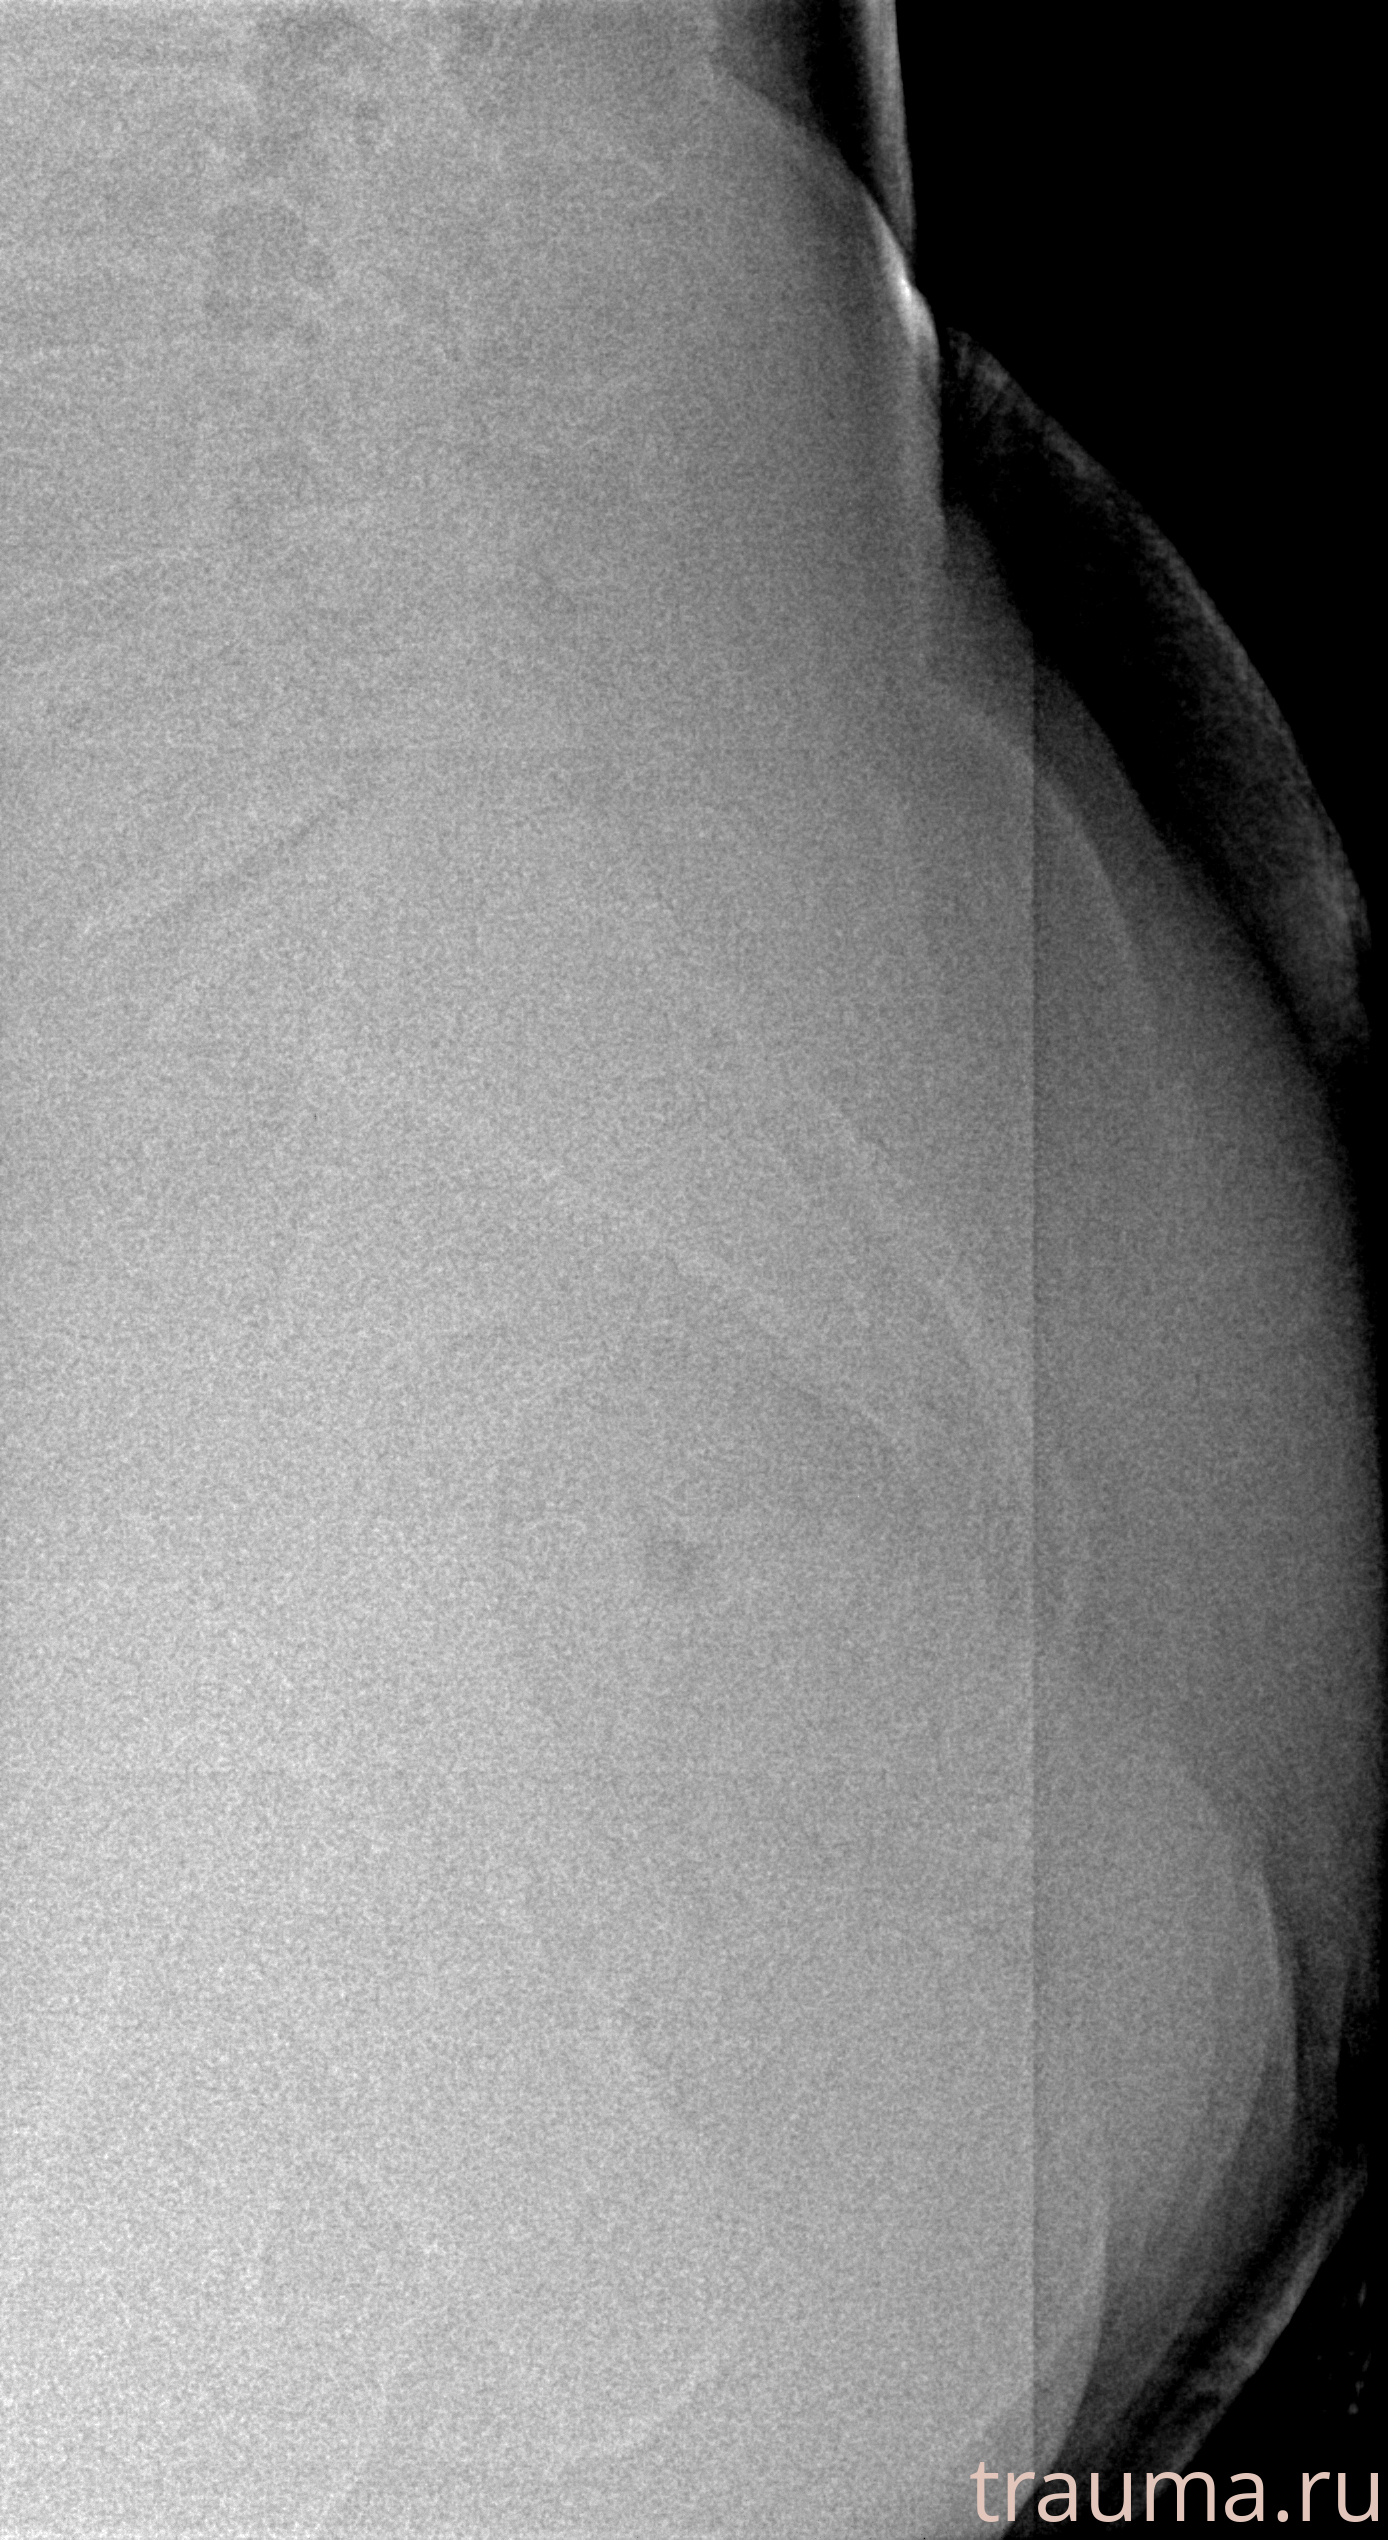

Рентгенограммы

Рентген на дому: по вашему адресу приезжает врач-рентгенолог, травматолог-ортопед с мобильным рентгеновским аппаратом, проводит диагностику травмы или заболевания, делает необходимые рентгенограммы, дает рекомендации по дальнейшему лечению. Получить качественные снимки в домашних условиях возможно благодаря уникальной методике, разработанной МосРентген Центром для института  Склифосовского

Яркость: 1   Контраст: 1   Инвертировать: 0 Увеличение: 1

Перетаскивайте мышь вверх/вниз для контраста, влево/право для яркости. Прокрутка колесом изменяет масштаб. Нажмите Сбросить для возврата к исходному изображению. При увеличении держите мышь в той области, которую хотите рассмотреть.